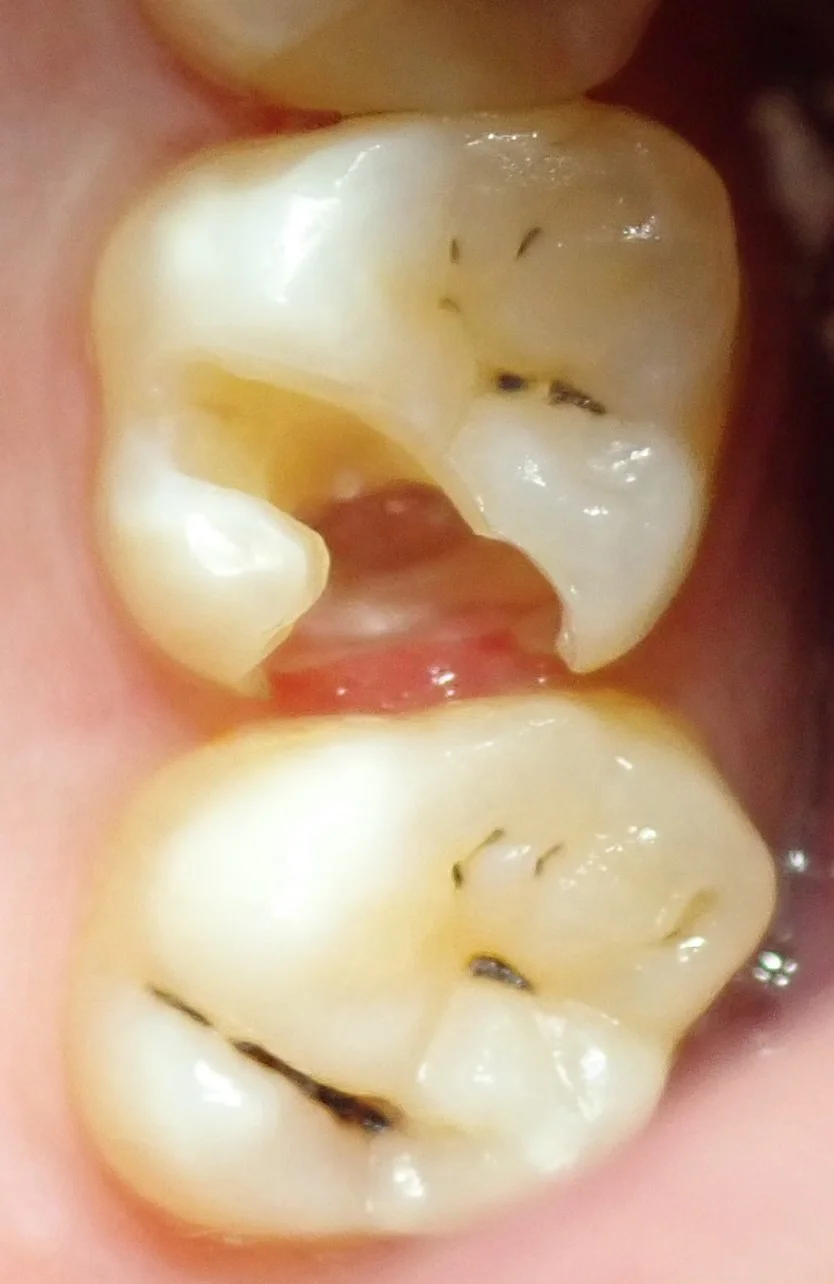

さて、では写真の方を。

まずは術前ですね。

お隣の県にて開業されている歯科医師の方です。

昔詰められた保険の白い詰め物が、大きく欠けて、中で虫歯になっているのが分かります。

・・・実は歯科医師の方って虫歯になっても放置してしまってる人結構多いんですよね。

忙しいってのはもちろんなんですけど、治療の技量が分かってしまう分、誰に依頼すればいいのか難しくなってしまうんです。

理想を言えば自費専門医だけど、都市部にしか居ないし・・・

ってことで、探した結果、程よい距離にうちがあったので、いらっしゃったって感じです。